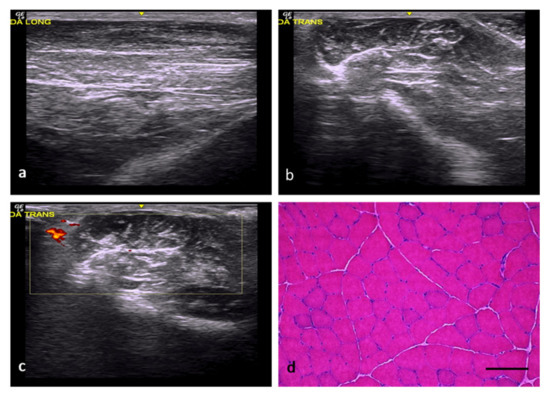

| Group | Identification of the Lesion | Edges of Lesion | Morphology of the Lesion | Increased Echogenicity | Echotexture Distortion | Vascularization |

|---|---|---|---|---|---|---|

| NC | — | — | — | Grade 0 | Grade 0 | Grade 0 |

| RC | Yes | poorly delimited | imprecise | Grade 1 | Grade 1 | Perilesional Grade 2 |

| FC | Yes | well delimited | angulated | Grade 3 | Grade 3 | Intralesional Grade 2 |

| AT | Yes | poorly delimited | imprecise | Grade 2 | Grade 1 | Intralesional Grade 1 |

| OS | Yes | well delimited | Variable (rounded, angled, or patchy) | Grade 3 | Grade 3 | Perilesional Grade 1 |

| DM | Yes | well delimited | Variable (rounded, angled, or patchy) | Grade 2 | Grade 3 | Intralesional Grade 1 |